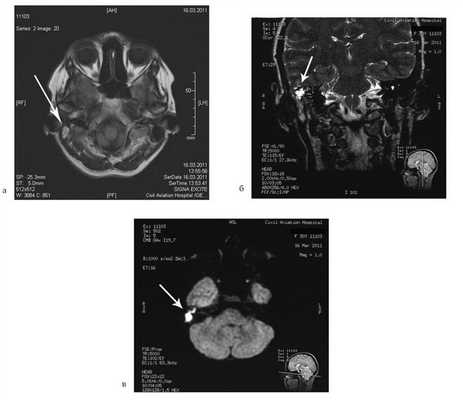

Пациентке была выполнена МРТ основания черепа по описанной методике (рис. 1). Рисунок 1. МРТ основания черепа больной Ф. с хроническим правосторонним гнойным средним отитом. Фистула лабиринта. Холестеатома. а — исследование в режиме Т1; б — в режиме Т2; в — в режиме non-EPI DWI.

В режиме Т1 справа определяется образование с низкой интенсивностью сигнала, а в режиме Т2 и non-EPI DWI — образование с гиперинтенсивным сигналом. Диагноз: хронический правосторонний гнойный средний отит; холестеатома; фистула лабиринта. Пациентка была подвергнута санирующей операции на правом ухе с тимпанопластикой и облитерацией паратимпанальных пространств. Были выявлены холестеатома, заполняющая аттик, адитус, антрум, деструкция цепи слуховых косточек, фистула латерального полукружного канала. Послеоперационный период протекал без особенностей, на 15-е сутки была удалена гемостатическая губка и силиконовая выстилка. При контрольном осмотре ухо сухое, отмечает улучшение слуха, головокружения нет. Через 12 мес проведено повторное МРТ-исследование. Признаков холестеатомы не обнаружено. Получен хороший функциональный результат — ухо толерантно к воде, самоочищается.